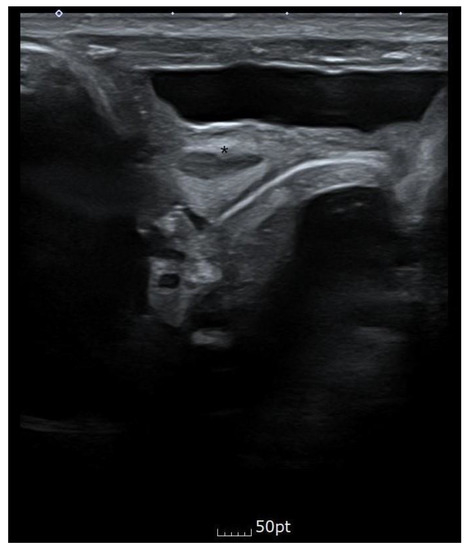

Bilateral renal pelvic dilatation was observed during the prenatal examination, but on day three after birth and approximately one month after discharge, the ultrasound showed that the right kidney was 3.1 mm and the left kidney was 4.5 mm, which were within the normal range. Abdominal ultrasonography showed that the cavity was asymmetric at the fundus level of the uterus, and a constricted protrusion was observed in the middle. The cervix and the surrounding space could be seen bilaterally, suspected bicornuate or septate uterus. Figure 4 shows the abdominal ultrasound findings.

Figure 4. When an abdominal ultrasound transverse section performed with a linear probe was performed, a bicornuate or septate uterus was suspected. Fundus level of the uterus, * a projection in the middle of the uterus.

During the prenatal examination, bilateral renal pelvic dilatation was observed. However, on day 3 of life and one month after birth, the right kidney was 3.1 mm, and the left was 4.5 mm, which was within the normal range. No specific findings were observed, other than a trend towards decreasing left pelvis AP diameter to 4 mm between 2 months and 19 days and three months and 12 days old. No specific indication of the suspected bicornuate or septate uterus was observed in the ultrasound. The decision was made to follow up on this suspicion.